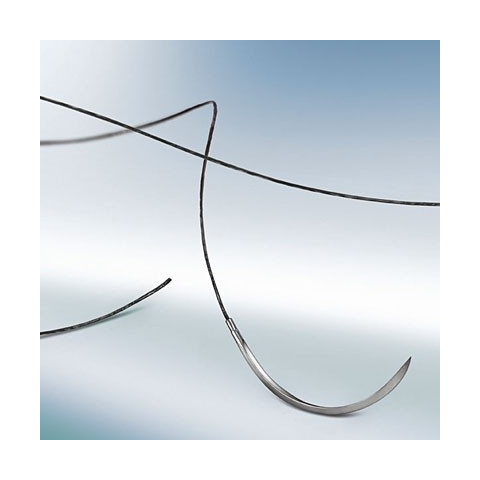

1 kép

1 kép Supramid fekete 5/0 (1) 45 cm DS19 tűvel

Kiszerelés: 36 db / doboz Supramid® Nem felszívódó varróanyag Leírás: A Supramid szintetikus nem felszívódó poliamidból készült varróanyag, amely a fonal átmérõjétől függõen kétféle kialakításban kapható: Supramid pseudo-monofil poliamid-6.6 sz